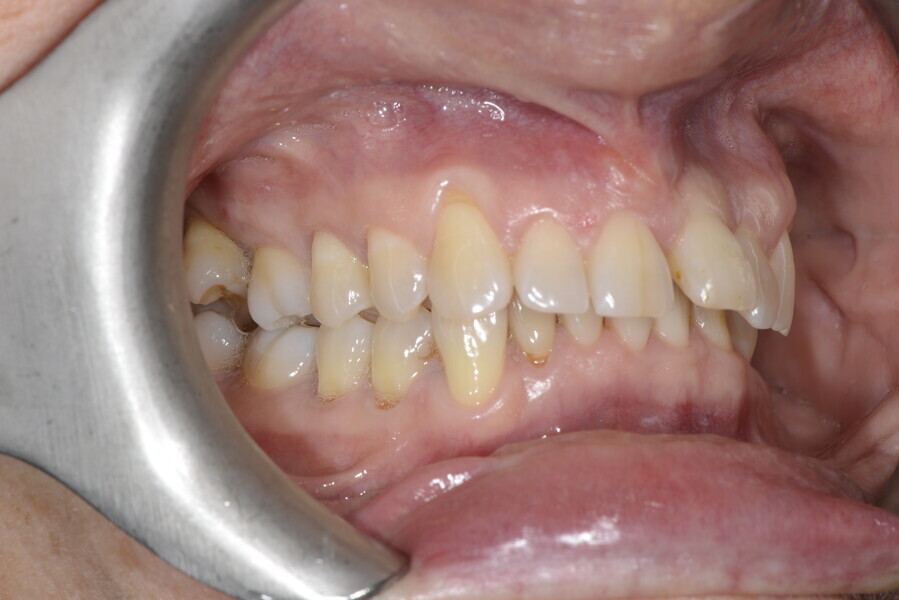

The 58-year-old patient wished to improve his oral aesthetics and function, complaining of mobility of the posterior teeth and wear of the anterior teeth. After data collection, a very complex situation was identified (Figs. 11–13):

1. severe periodontitis with poor prognosis of some teeth;

2. anterior crossbite;

3. severe wear mainly of the anterior teeth and compensatory eruption;38

4. atypical swallowing and lower posture of the tongue at rest;

5. masticatory dysfunction during the mastication test; and

6. no significant signs of temporomandibular disorder.